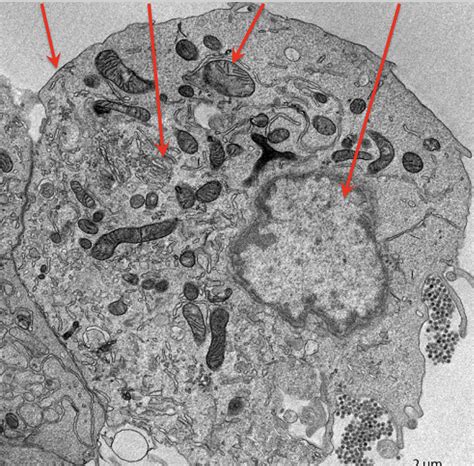

Alright, let’s kick things off with the absolute basics, shall we? Pseuoschistosome side 13 is, at its core, a type of parasitic worm. When we talk about parasites, we’re generally referring to organisms that live on or inside another organism, called a host, and benefit by deriving nutrients at the host’s expense. Pseuoschistosomes are part of a larger group of flatworms, and the specific ‘side 13’ designation often refers to a particular strain, species, or even a specific genetic marker that scientists use to differentiate it from others in its family. Think of it like having different breeds of dogs – they’re all dogs, but they have distinct characteristics. Similarly, Pseuoschistosome side 13 has its own unique features that set it apart. Its life cycle is typically complex, involving multiple hosts and different developmental stages. This complexity is a hallmark of many parasites and is a key area of study for researchers trying to understand how they survive and spread. The ‘side 13’ might come from how it was first identified or a specific genetic sequencing result, helping scientists pinpoint its identity. This level of detail is crucial for tracking its presence, understanding its behavior, and developing strategies to manage any associated health concerns. It’s not just a random label; it’s a scientific identifier that unlocks a wealth of information about the parasite’s lineage and characteristics. So, when you hear ‘Pseuoschistosome side 13,’ picture a very specific, uniquely identified parasitic flatworm with a potentially intricate life story. This specificity is what allows for targeted research and intervention, making it a vital point of focus in parasitology. We’re talking about a microscopic marvel of adaptation, and ‘side 13’ is just the key to unlocking its specific biological narrative. It’s the difference between knowing you have a cold and knowing you have a specific strain of the rhinovirus – precision matters in science!

Now, let’s get into the really fascinating stuff: the life cycle of Pseuoschistosome side 13 . Parasites are masters of survival, and their life cycles are often incredibly complex, designed to ensure they can reproduce and spread effectively. For Pseuoschistosome side 13, this typically involves at least two different host species. Usually, there’s an intermediate host, which is often a snail or another mollusk, and a definitive host, which is where the parasite reaches sexual maturity and reproduces, often a vertebrate like a fish, bird, or even a mammal. The cycle might start with eggs being shed into the environment, perhaps in water or feces. These eggs hatch into a larval stage, which then needs to infect the intermediate host – let’s say, a specific type of snail. Inside the snail, the parasite undergoes significant development and multiplication, often through several more larval stages. This is where the ‘side 13’ might be particularly relevant, as certain genetic variations could influence its infectivity or development within specific snail species. Once it’s developed sufficiently within the snail, a new larval form emerges, ready to infect the definitive host. This stage is often the one that poses a potential risk. For instance, if humans accidentally ingest contaminated water or come into contact with infected intermediate hosts, they could become infected. Inside the definitive host, the parasite matures into an adult worm, mates, and lays eggs, thus completing the cycle and perpetuating the species. Understanding each step – from egg to larva to infective stage – is crucial for figuring out how to break the cycle. This might involve controlling the snail population, improving sanitation to prevent contamination, or educating communities about the risks. The ‘side 13’ designation can be vital here, as different strains might prefer different hosts or have varying levels of infectivity, requiring tailored control strategies. It’s a delicate dance of adaptation and survival, and studying this cycle gives us the upper hand in preventing infections. The sheer ingenuity of these organisms in navigating their multi-host existence is truly remarkable, showcasing nature’s relentless drive for continuation. Each stage is a critical bottleneck, and Pseuoschistosome side 13 has evolved to overcome them all.